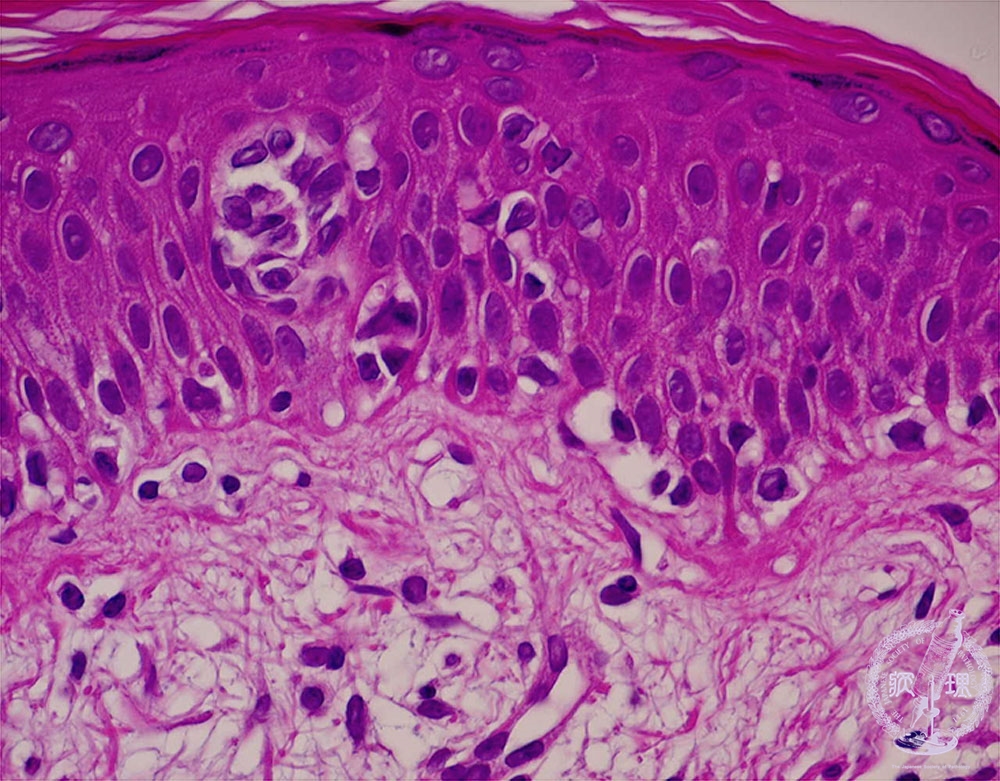

- (11)Malignant lymphoma of the skin (Mycosis fungoides)

Atypical lymphocytes infiltrate the epidermis with a microabscess (inside a circle).